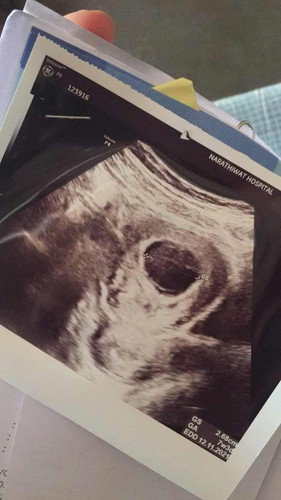

สวัสดีคะอยากสอบถามนิดนึงคะพออดีดิฉันไปอัตราซาวนด์ท้องหมอบอกว่าพบเเค่ถุงคครภ์มีใครพอเเนะนำบ้าง

เเบบนี้มีสิทธิเจอเดกไม่คะ

บ้านนี้ไปฝากครั้งแรกซาวด์ไม่เจออะไรเลยค่ะ หมอนัดอีก2สัปดาห์ ไปซาวด์เจอถุงตั้งครรภ์ยังไม่เจอน้องค่ะ แล้วนัดอีก 2 สัปดาห์ไปซาวด์เจอน้องแล้วค่ะตอนนั้นน้องได้ 8w แต่ถ้านับตามประจำเดือนจะ 10w ตอนนี้ 17w แล้วค่ะ ใจเย็นๆนะคะ

รอซาวด์อีกรอบดีกว่าค่ะ อย่าพึ่งกังวลนะค่ะ ของเราซาวด์ครั้งแรกไม่เจอเหมือนกัน คือไม่เจออะไรเลย หมอนับได้10วีค ที่จริงมัน6วีคเองค่ะ ตอนนั้นใจหายเหมือนกัน พอมาซาวด์อักรอบ เจอค่ะ

บ้านนี้เจอตอน 6 วีค แต่ซาวด์ผ่านช่องคลอด ตอนซาวด์ผ่านหน้าท้องก็ไม่เจอเหมือนกันค่ะ หมอเลยซาวด์ผ่านช่องคลอดให้ คุณแม่ใจเย็นๆนะคะ อย่าคิดมาก

บ้านนี้ตอน7W ก็ไม่เจอน้องค่ะ หมอนัด2สัปดาห์ถัดมาเจอหัวใจน้องตอน9Wค่ะ คุณแม่ใจเย็นๆนะค่ะ อย่าคิดมาก อายุครรภ์อาจจะยังน้อยอยู่ค่ะ

ของเราซาวหน้าท้องตอน6 วีคเจอเเค่ถุงครรภ์ ซาว์ดอีกทีตอน 8วีค ซาว์ผ่านช่องคลอด เจอตัว มีหัวใจเต้น ทุกอย่างปรกติดีค่ะ

เราซาวด์ตอน 7 w เจอแต่ถุงตั้งครรภ์ หมอบอกเพราะครรภ์ยังอ่อน นัดอีกทีตอน 12 w เจอตัวน้องและหัวใจเต้นค่ะ

อายุครรภ์น่าจะยังน้อยนะคะ สัก9วีค ไปซาวใหม่นะคะ เพราะเราไปซาวตอน9วีคแล้วพบค่ะ (ซาวช่องคลอด)

เราเคยเจอตรวจเจอแต่ถุงตั้งครร์เรา10วีคก็ไม่เห็นเด็กหมอบอกว่าอาดจะเป็นท้องลมค่ะ

ปีที่แล้วเป็นคะ ตัวอ่อนไม่สมบูรณ์ เดี๋ยวร่างกายขับออกเป็นประจำเดือนเองคะ

รออีกซักพักน่ะค่ะ ครรภ์ยังอ่อนอยู่ ไว้ไปซาวน์ใหม่ตัวอ่อนอาจจะโตแล้วก็ได้ค่ะ